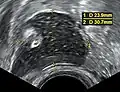

Vaginal and ovarian dermoid cysts

Ovaries normally grow cyst-like structures called follicles each month. Once an egg is released from its follicle during ovulation, follicles typically deflate. Sometimes fluid accumulates inside the follicle, forming a simple (containing only fluid) cyst.[2] The majority of these functional cysts resolve spontaneously.

While all ovarian cysts can range in size from very small to quite large, dermoid cysts are not classified as functional cysts. Dermoid cysts originate from pluripotent germ cells (which are present at birth) that differentiate abnormally, developing characteristics of mature dermal cells. Complications exist, such as torsion (twisting), rupture, and infection, although their incidence is rare. Dermoid ovarian cysts which are larger present complications which might require removal by either laparoscopy or laparotomy (traditional surgery).[3][4] Rarely, a dermoid cyst can develop in the vagina.[5][6][7]